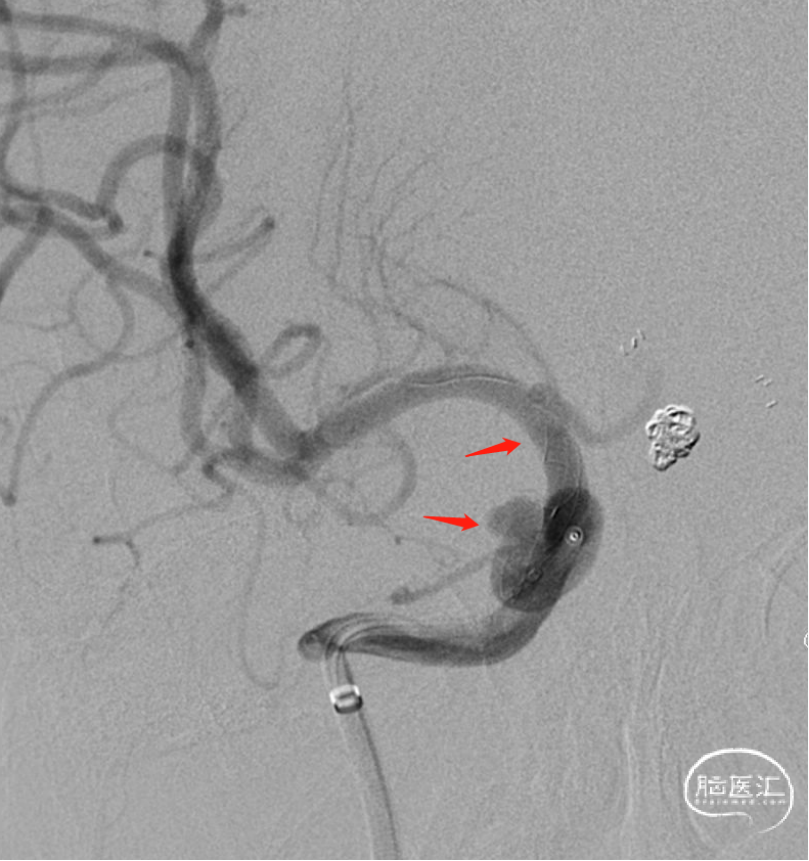

现病史:患者五年前因前交通动脉瘤破裂出血就诊于我科行脑动脉瘤栓塞术,术后患者恢复良好;但患者未规律复查评估动脉瘤愈合情况;

术前诊断:前交通动脉瘤栓塞术后复发

4、微导丝顺利通过前交通动脉,微导丝进入右侧A2,微导管跟进,开始栓塞弹簧圈;栓塞后引入并释放Atlas动脉瘤辅助支架,继续填塞弹簧圈

5、术后即刻影像,复查造影示动脉瘤栓塞密实,载瘤动脉通畅